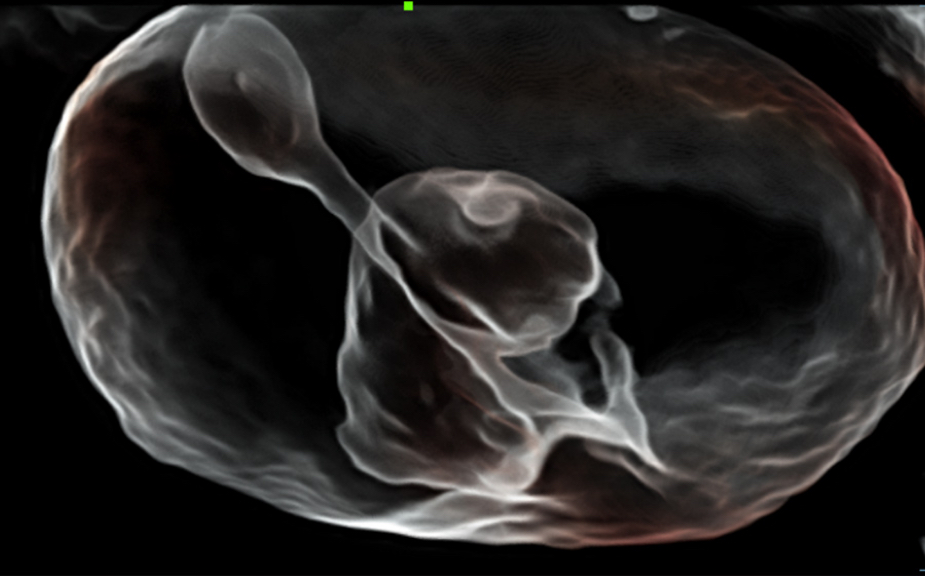

The Nuewa I9, dedicatedly designed for women and neonatal healthcare, providing an innovative experience from inside out.?These innovations are developed based on in-depth insights into complex clinical scenarios, providing accurate and timely answers as well as outstanding efficiency and remarkable user experience.

Clinical Images